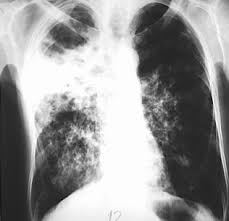

Tuberkulosis atau TBC adalah penyakit yang sangat mudah sekali dalam penularannya. Seperti halnya penyakit flu biasa, dalam penyebaranya TBC juga melalui udara. Penyakit TBC sangat mematikan apabila tidak segera dilakukan penanganan. Di Indonesia, penanganan sejak dini sudah dilakukan dengan memberikan paket imunisasi BCG pada balita. Namun demikian, belum sepenuhnya Indonesia 100% terbebas dari penyakit TBC ini.

TBC adalah merupakan suatu penyakit yang tergolong dalam infeksi yang disebabkan oleh bakteri Mikobakterium tuberkulosa. Penyakit TBC dapat menyerang pada siapa saja tak terkecuali pria, wanita, tua, muda, kaya dan miskin serta dimana saja. Di Indonesia khususnya, Penyakit ini terus berkembang setiap tahunnya dan saat ini mencapai angka 250 juta kasus baru diantaranya 140.000 menyebabkan kematian. Bahkan Indonesia menduduki negara terbesar ketiga didunia dalam masalah penyakit TBC ini.

Pada umumnya penularan TBC terjadi secara langsung ketika sedang berhadap-hadapan dengan si penderita, yaitu melalui ludah dan dahak yang keluar dari batuk dan hembusan nafas penderita. Secara tidak langsung dapat juga melalui debu, alat makanan dan minuman yang mengandung kuman TBC. Melalui medium air, TBC juga bisa bertahan dan menyebar. Lamanya dari terkumpulnya kuman sampai timbulnya gejala TBC dari yang berbulan-bulan sampi tahunan membuat penyakit TBC ini digolongkan penyakit kronis.